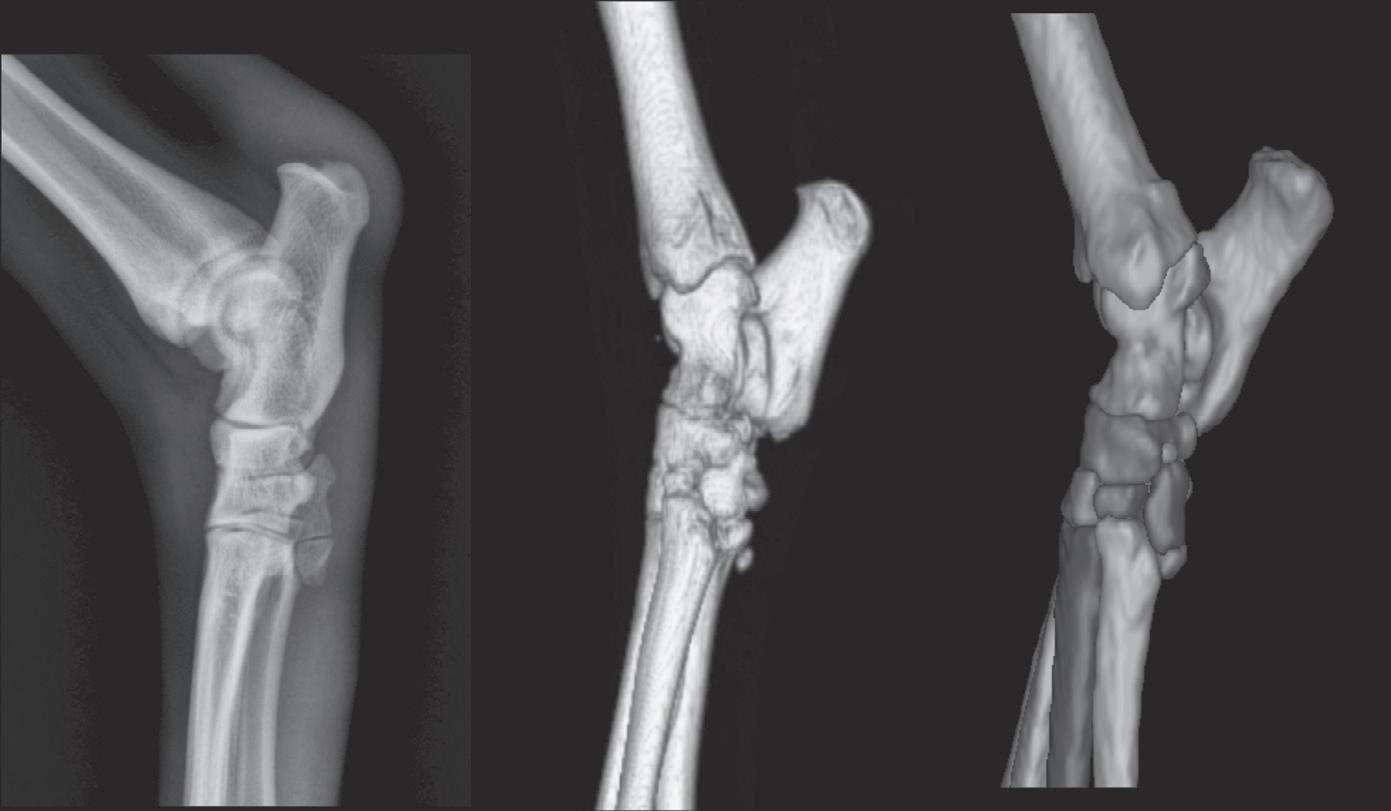

Figure 1-10. The left panel is a medial-lateral radiograph of a canine tarsus. The middle panel is a three-dimensional rendering of a normal right canine tarsus as seen from the perspective of the x-ray beam when making a medial-lateral radiograph. The right panel is identical to the middle panel, but where each bone has been colorized (see Color Plate 2). Colorizing makes it easier to comprehend the extent of overlap. Note in the radiograph that the only edges that can be evaluated are the dorsal and plantar edges. The proximal edge of the calcaneus is also visible in this projection because it is not superimposed on any other structure.